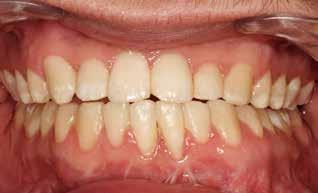

SAGBAKKEN P, KJELLERUP AD, STARCH-JENSEN T

Mandibulær midtlinjedistraktionsosteogenese til korrektion af transversel okklusionsafvigelse / 590

I den næste artikel vender vi os mod ortodontiskkirurgisk behandling. Emnet er transversel udvidelse af mandiblen ved midtlinjedistraktionsosteogenese. Dette illustreres og gennemgås i en interessant kasuistik. Vi har også her tidligere bragt artikler om distraktionsosteogenese. I 2021 såvel en oversigtsartikel om emnet som en kasuistik om unilateral mandibulær distraktionsosteogenese. I dette nummer bringes en kasuistik om en 15årig dreng med vækstbetinget kæbedeformitet med betragtelig transversel okklusionsafvigelse, der korrigeres med ortodonti og mandibulær midtlinjedistraktionsosteogenese. Behandlingen angives som forudsigelig, om end med betydelig risiko for recidiv samt diverse komplikationer. Derfor anbefales behandlingen udelukkende til ekstreme vækstbetingede transverselle okklusionsafvigelser.